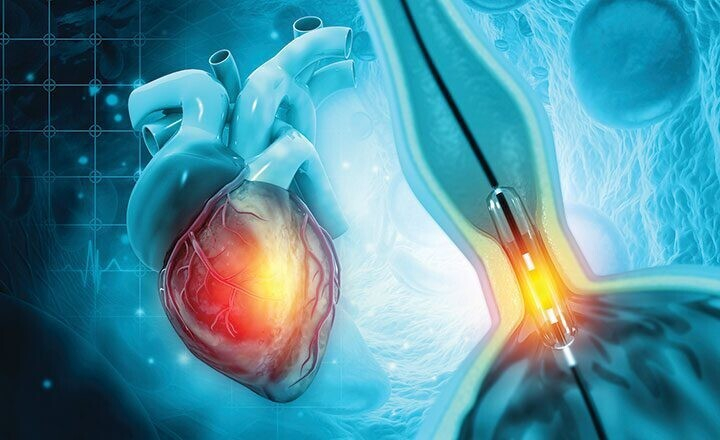

Коронарография (коронарная ангиография) — высокоточный метод диагностики поражений сосудов сердечной мышцы. Это малоинвазивная процедура, позволяющая получить детализированное изображение сосудов органа благодаря предварительному введению контрастного вещества. Коронарография — одна из наиболее информативных процедур в кардиологии, позволяющая точно определять сосудистые патологии.

В ходе проведения манипуляции выполняют прокол вены для введения катетера, который приближается к исследуемому органу. Ход катетера постоянно контролируется специалистом. Контрастное вещество поглощает рентгеновский лучи и позволяет сформировать четкую картину сосудов сердца на мониторе.